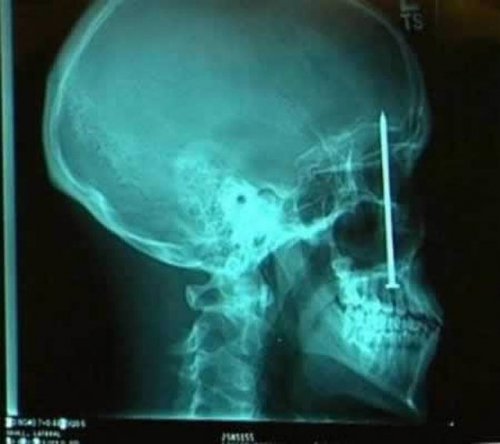

Стоматолог обнаружил источник зубной боли. Патрик Лоулер (Patrick Lawler) жаловался на боль вдоль нёба его рта: как оказалось, причиной был 10 сантиметровый гвоздь, который строитель нечаянно вставил в свой череп шестью днями ранее.

5-сантиметровый гвоздь, который можно заметить на этом рентгеновском снимке, был обнаружен после того, как мужчина из Сеула, Южная Корея, обратился в больницу с сильной головной болью. После обследования и опроса мужчины врачи предположили, что гвоздь был результатом несчастного случая, произошедшего четыре года назад, но мужчина не заметил, что в его голове был гвоздь.